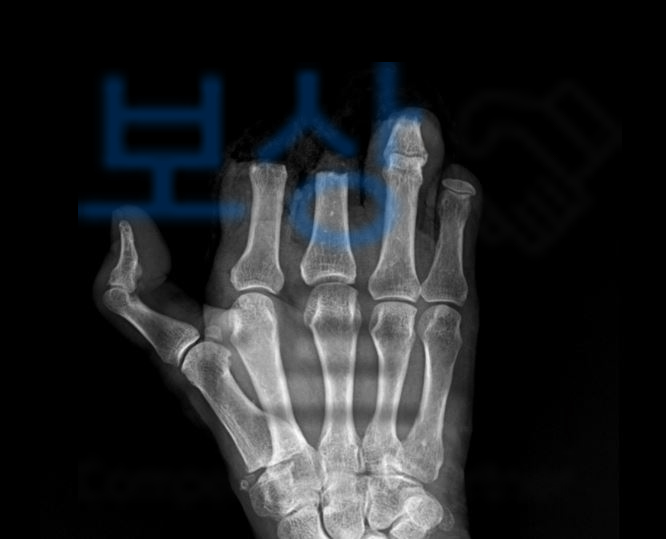

위 끔찍한 사고로 인해 배@@님은 오른손 2-4수지 절단 및 개방성골절 진단을 받으셨습니다.

절단된 손가락의 손상이 심하고 손가락의 형태가 불분명하여 접합수술을 하였지만 괴사하게 되었고 결국 절단을 하실 수 밖에 없는 상황이 되었습니다.

그 후 보험사에 발급된 장해진단서를 기초로 후유장해보험금을 청구하게 되었는데요, 보험사에서는 높은 장해율에 재해 당시 상황을 조사하기 위해 치료경과 진료기록 일체와 mri 및 x-ray자료, 의료정보열람위임장을 요청하였습니다.